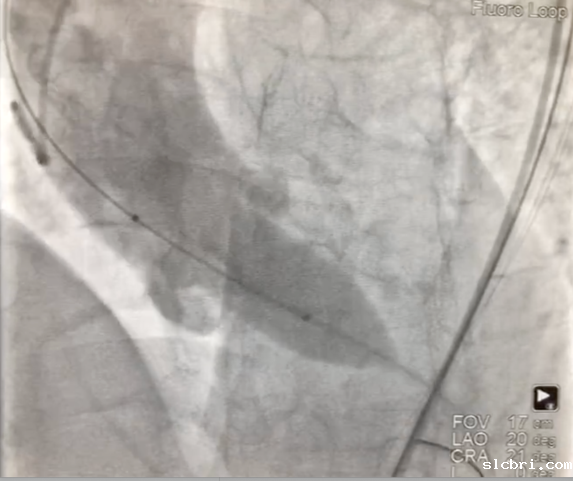

1、经右股动脉将Emboshield Nav6放栓塞装置输送至左、右颈内动脉。

2、经左股动脉入路,顺利跨瓣后,选取20 mm球囊于180 bpm下快速起搏预扩,显示无漏,左、右冠脉未受影响,但可见左冠窦、无冠窦巨大钙化团块。